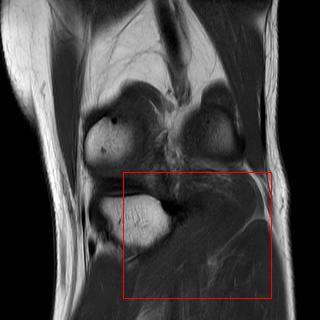

Puhhh, das sind ganz schön viele Bilder, Bud Hill. Ich werde sie in ein paar Tagen löschen. Also, das Knie(Gelenk) scheint mir auf den ersten Blick tatsächlich in Ordnung zu sein. Was mir allerdings, nach mehrmaliger durchsicht und vergleiche mit anderen Bildern im Netz aufgefallen ist, dass mit dem "Popliteus" Muskel etwas nicht stimmt. Das könnte von den Symptomen her auch passen. Ich velinke dich am Besten mit einer Seite dazu, die eigentlich alles darüber aussagt. https://www.muskel-und-gelenkschmerzen.de/triggerpunkte/triggerpunkte-selbst-behandeln/popliteus/ Mehr sag i net...1 point

Wie heißt es so schön - das Knie ist es nie! Man muss auch mal über dem Tellerrand hinausschauen. Das ist immer der selbe Fehler, den viele Kollegen machen. Auch wenn am Kniegelenk tatsächlich ein Schaden ersichtlich wäre, ist es gaaaaanz selten, dass die Ursache das Knie selber ist. Das müsste z.B. durch einen Sturz oder durch eine Verdrehung direkt verletzt worden sein. Man müsste erst mal verschiedene Funktionstests der einzelnen Gelenke durchführen, die (in)direkt mit dem Knie verbunden sind. Das wäre: Becken(ISG), Hüfte, Wadenbein, Sprunggelenk(obere) und das Knie selber auf evtl. Blockaden prüfen. Das letztere wäre meine eigentliche Vermutung. Deine Symptome deuten so ziemlich auf eine Blockade im Kniegelenk selber hin. Denn selbst ein Meniskus kann durch eine Blockade eingeklemmt sein. An deiner Stelle würde ich mir jemanden suchen, der dir deine Knochen zurecht rückt! Am Besten einen Ostopathen oder einen Chiropraktiker. Hier ein Beispiel wie das aussehen sollte: https://www.youtube.com/watch?v=rHJOH_ZblKI1 point

Hallo Bud, das klingt ja alles garnicht so schön was du da beschreibst. Ich hätte da erstmal ein paar Fragen - was war denn die Diagnose die auf dem Rezept drauf stand? Was hast du denn bekommen? Manuelle Therapie, Krankengymnastik? Die Therapeuten bei denen du warst, haben keine Tests mit dir gemacht? Wurde das MRT mit Kontastmitteln gemacht oder ohne? Dass man entzündliche Prozesse besser erkennen kann? Was mir so in den ersten Sinn kam, dass es mögliherweise eine muskuläre Dysbalance sein könnte - dass deine vordere Oberschenkelmuskulatur viel kräftiger ist als die Rückseite und damit die Zugkräfte sich ändern. Wenn du Pistolsquats machen kannst, gehe ich davon aus, dass dein Gleichgewicht und Stabilität in der Unteren Extremität ausreichend vorhanden ist. Eine Längenmessung wäre mal ganz interessant wie lang die jeweiligen Knochen sind. Genauso interessant wäre auch das MRT-Bild zu sehen. Wenn du es hast und hochladen oder mir zuschicken möchtest, wäre das sicher auch interessant. LG1 point